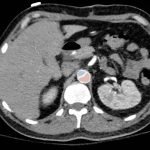

Chest x-ray and CT angiogram was performed to evaluate his thoracic and abdominal vasculature. Chest x-ray did not show any significant widening of the mediastinum. The CT angiogram demonstrated an intimal tear along the aortic arch separating a true and false aortic lumen, consistent with an acute aortic dissection. The true lumen (highlighted in blue in images 1-5) can be identified by continuity with an undissected part of the aorta1. While the false lumen (highlighted in red in images 1-5) can be identified by its crescent shape and larger cross-sectional area.1